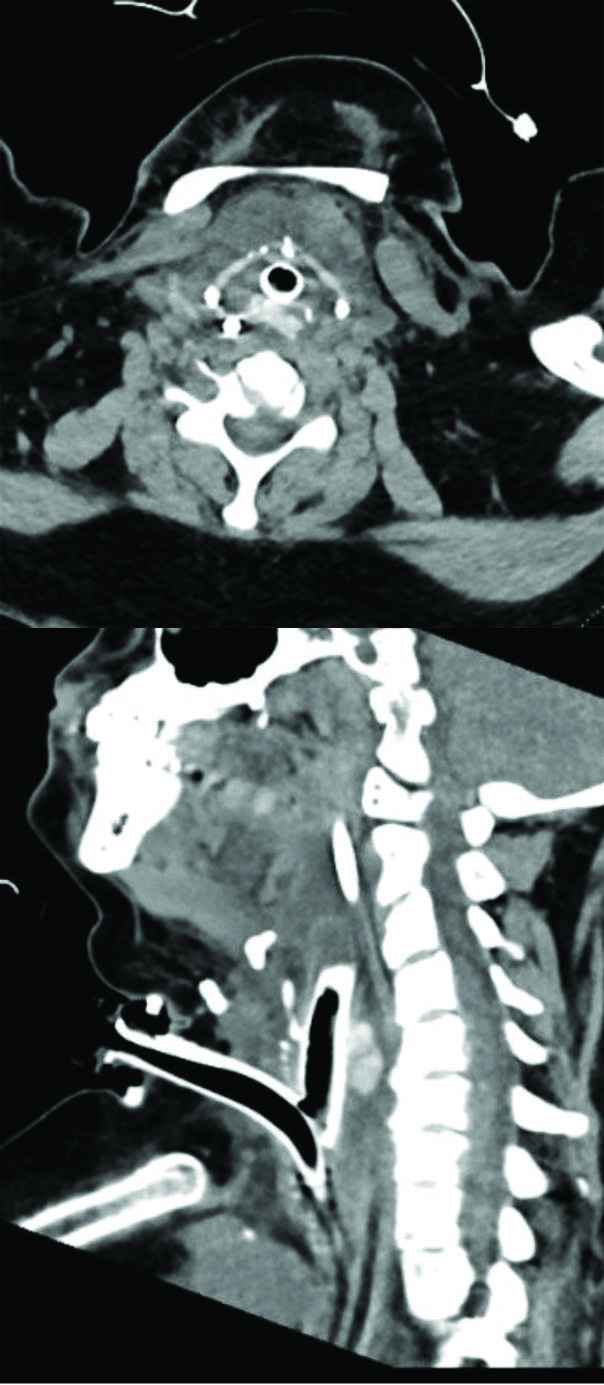

This is a female in her 40s who is a patient of Dr. Liang's. She had a prolonged intubation and developed severe posterior glottic stenosis along with Grade 4 100% subglottic stenosis.

Figure 4. Postoperative CT scan showing the cartilage graft in place with a tracheostomy tube and a suprastomal stent